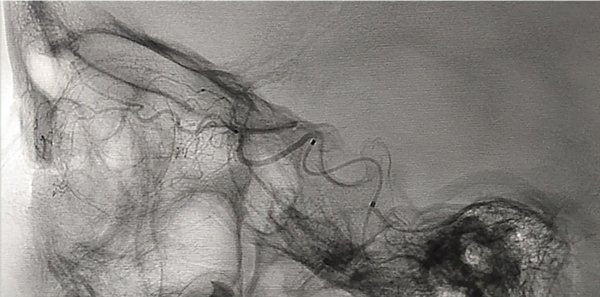

Puede presentarse la situación de observar escaso reflujo hacia la arteria carótida interna durante la adquisición superselectiva, esto no disminuye la efectividad siempre y cuando se logre una correcta opacificación de la coroides y se inyecten las drogas de manera pulsada y suave, según lo descripto por Jabbour et al. Si la maniobra no es satisfactoria se vuelve a repetir este paso. Si luego de dos (hasta tres) maniobras no se consigue cateterizar la arteria oftálmica se asume que no tiene un ostium “favorable” por lo que se da lugar a la siguiente fase de la técnica. Se posiciona el microcatéter en la arteria carótida externa y se cateteriza super-selectivamente la arteria meníngea media (o meníngea accesoria) para visualizar la anastomosis con arteria oftálmica (técnica 2 en 2 completa, fig. 5 y 6).

Fig 5: Cateterización superselectiva de arteria meníngea media (AMM) derecha, se observa anastomosis con arteria oftálmica homolateral y correcta opacificación de la coroides. Técnica “en dos pasos” o técnica “2 en 2 completa”. Vista lateral estricta. Microcatéter Magic 1.5.